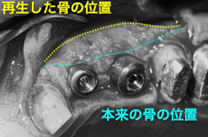

(図説)生体親和性の高い材料(骨補填材、吸収性遮断膜)を使用し、骨の再生治療を行った。

(図説)術後5ヶ月の状態。再生した骨によってインプラントが完全に覆われる。

インプラントが露出していた部位には、インプラントの安定に必要十分な骨が再生した。